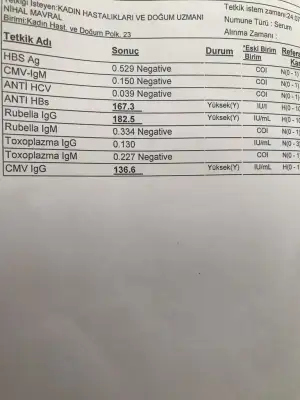

Tahliller güzel çıkmış. Yüksek olan değerler o hastalıklara karşı bağışıklığınız olduğunu gösteriyor.Kızlar bir bakarmısınız tahlil sonuçlarıma☺